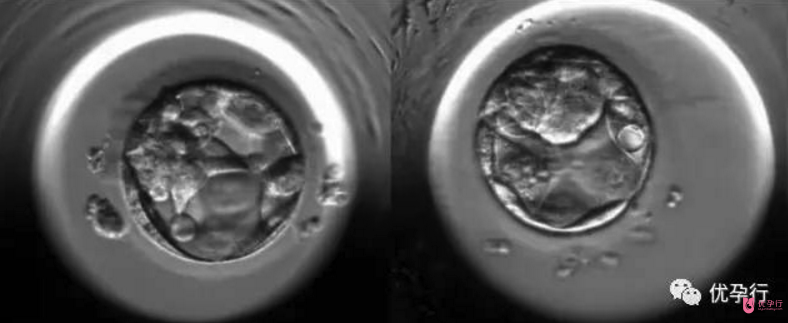

囊胚

桑葚胚的細胞繼續分裂,細胞間逐漸出現小的腔隙,大約2天后它們較后匯合成一個大腔,桑葚胚轉變為中空的胚泡。胚泡也就是囊胚,這個時候是受精卵成活的第5天。早期胚胎發育到囊胚的這兩天是非常關鍵的,對溫度、空氣含氧量、二氧化碳含量的要求都非常高。

囊胚因為比胚胎在體外存活的時間要長,而且分裂出的細胞數量也要多出很多,從體積上來比,也要超出胚胎很多,因此更好的加大了著床的成功率。由此可以知道,試管嬰兒的囊胚移植是成功率較高的。